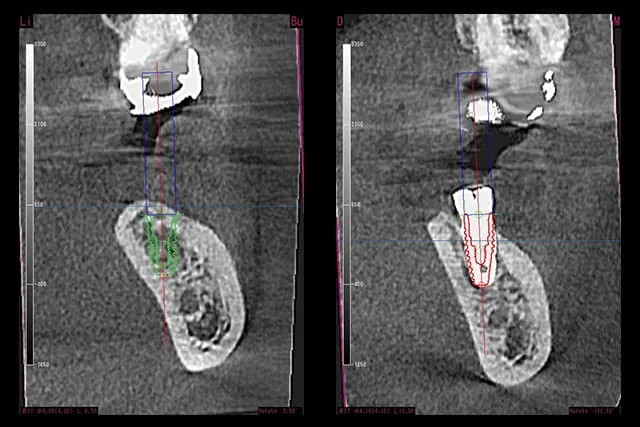

ガイデッドサージェリー(Guided Surgery)とは、CT撮影で得られたデータからコンピュータ上で埋入シュミレーションを行い、その結果を基に設計したマウスピース状のサージカルガイド(手術補助装置)を用いてインプラント埋入を行い、より安全性を向上させた手術方法のことです。

ガイドを使わずフリーハンドで埋入するよりも、埋入位置や埋入角度・決められたポイントに埋入する精密さなどを高めることができるため、近年ではますますガイドサージェリーの需要が高まってきています。

One Guide

「One Guide」は当院で使用しているインプラント体を製造しているメーカー「OSSTEM(オステム)」社の提供するガイドシステムです。当院のプレミアムプランではこのOne Guideを使用して、患者様の負担や出血をできるだけ少なく抑えた、低侵襲でより安心・安全な埋入手術を行います。

シュミレーション前後の違い